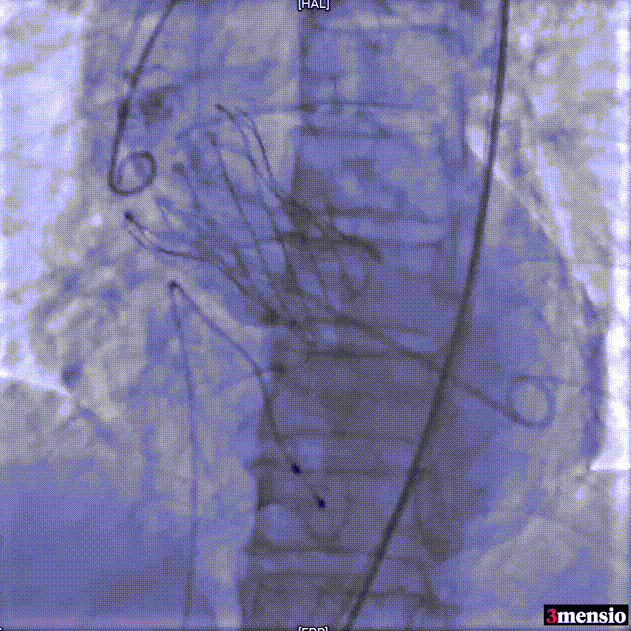

瓣膜释放至工作位评估

瓣膜脱钩

25mm球囊后扩

瓣膜最终形态